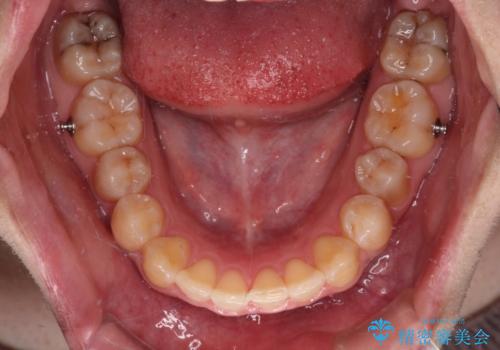

- インビザライン

舌の突出癖改善がうまくいかず、途中で舌小帯の切除を行いました。

気になる段差を納得いくまで改善させたため、治療期間は長くなりましたが、綺麗な仕上がりとなりました。